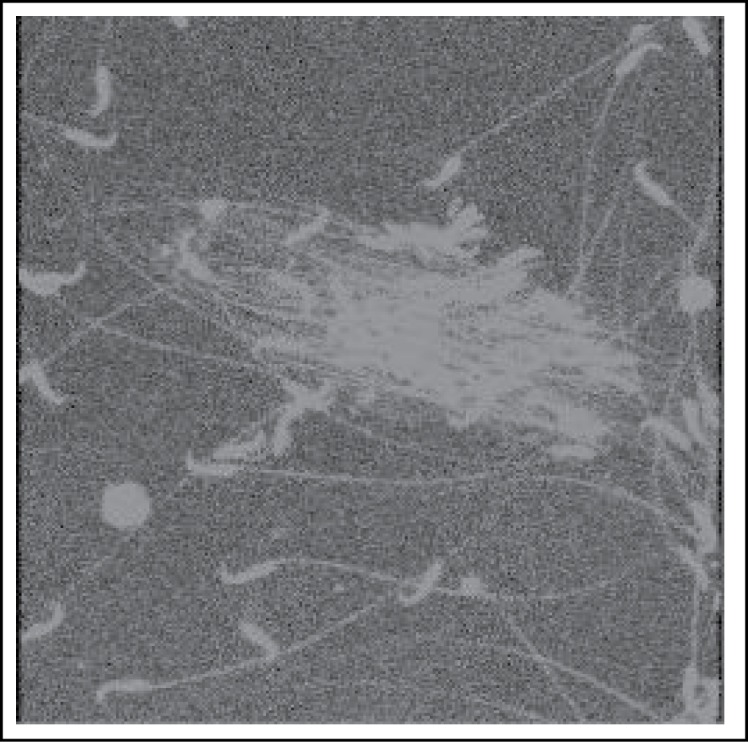

Figure 6 :

90 Day - Maturation Arrest Confocal micro scopic view shows agglutinated sperms dimentions 512X512

There was a significant reduction in serum testosterone level in acute as well as in chronic noise exposed groups (Table 1, Chart 1). The testis showed normal histological pattern in acute groups (Figure 2). Each testis is subdivided by connective tissue septa into lobules. Each contained numerous highly coiled semeniferous tubules. Each seminiferous tubule is lined by the stratified germinal epithelium, consisting of two major types of cells, the proliferating spermatogenic cells and nonproliferating supporting sustentacular cells or sertoli cells. Surrounding the seminiferous tubules were numerous blood vessels, various connective tissue cells, clusters of epitheloid cells and the interstitial cells of Leydig. Changes were seen in the histological pattern in 60-day (Figure 3,4) and 90-day (Figure 5,6) exposure groups. The seminiferous tubules were shrunken so that there was a space between the septum and the tubules. This type of change was noticed in the central part of the tubules only. The peripheral parts of tubules were compact and normal. Moreover maturation arrest in the germinal layers were noticed in some tubules. The basement membrane was broken and the germ cells sloughed into the interstitium. This was more advanced in 90 day exposure group. The sperms in the epididymis showed agglutination both under the light microscopy and confocal microscopy (Figure 8).

Transient increase in serum corticosterone and transient decrease in serum testosterone were observed during each period of noise and immobilization stress. Also enhanced testicular germ cell apoptosis was seen. (23, 26, 27). Low testosterone production (28) adversely affects the quality of ejaculates and subsequent fertility. The decrease in testosterone level is also associated with the marked reduction in epididymal sperm number (22). Moreover the epididymal sperms were agglutinated in noise exposed chronic group and the number of dead sperms were increased (29). So alterations in the normal testicular morphology associated with maturation arrest in the germinal cells was found and is similar to those findings following DPP treatment (20, 22, 30, 31).